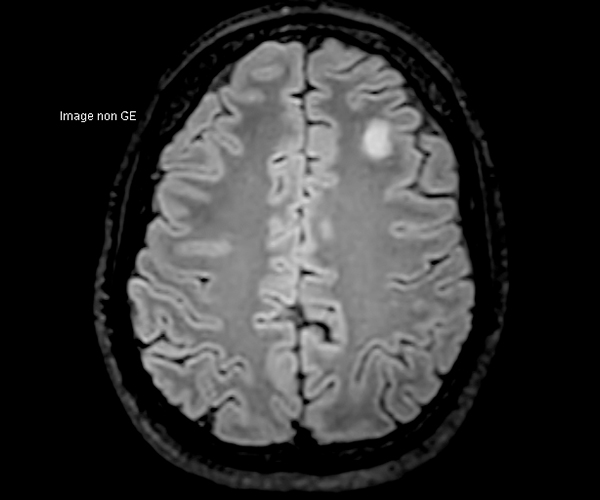

Concernant l’imagerie cérébrale, l’IRM 3T permet d’augmenter la sensibilité de détection de lésions ischémiques aiguës de petite taille, notamment chez les patients adressés pour accident ischémique transitoire (accident vasculaire cérébral), grâce à la séquence de diffusion dont le signal et la résolution sont augmentés.

L’amélioration de la résolution spatiale s’applique à l’exploration morphologique des hippocampes dans le diagnostic de la maladie d’Alzheimer, à la détection de petites lésions de sclérose en plaques ou de métastases, à l’étude fine du cortex dans les épilepsies.

L’augmentation de l’effet de susceptibilité magnétique à plus haut champ permet d’améliorer la détection des hémorragies et est utilisé également dans l’imagerie de perfusion (tumeurs) et l’IRM fonctionnelle (BOLD). L’allongement du T1 à plus haut champ entraîne une meilleure saturation des tissus statiques et par conséquent une augmentation du contraste sang/tissus dans l’AngioIRM.